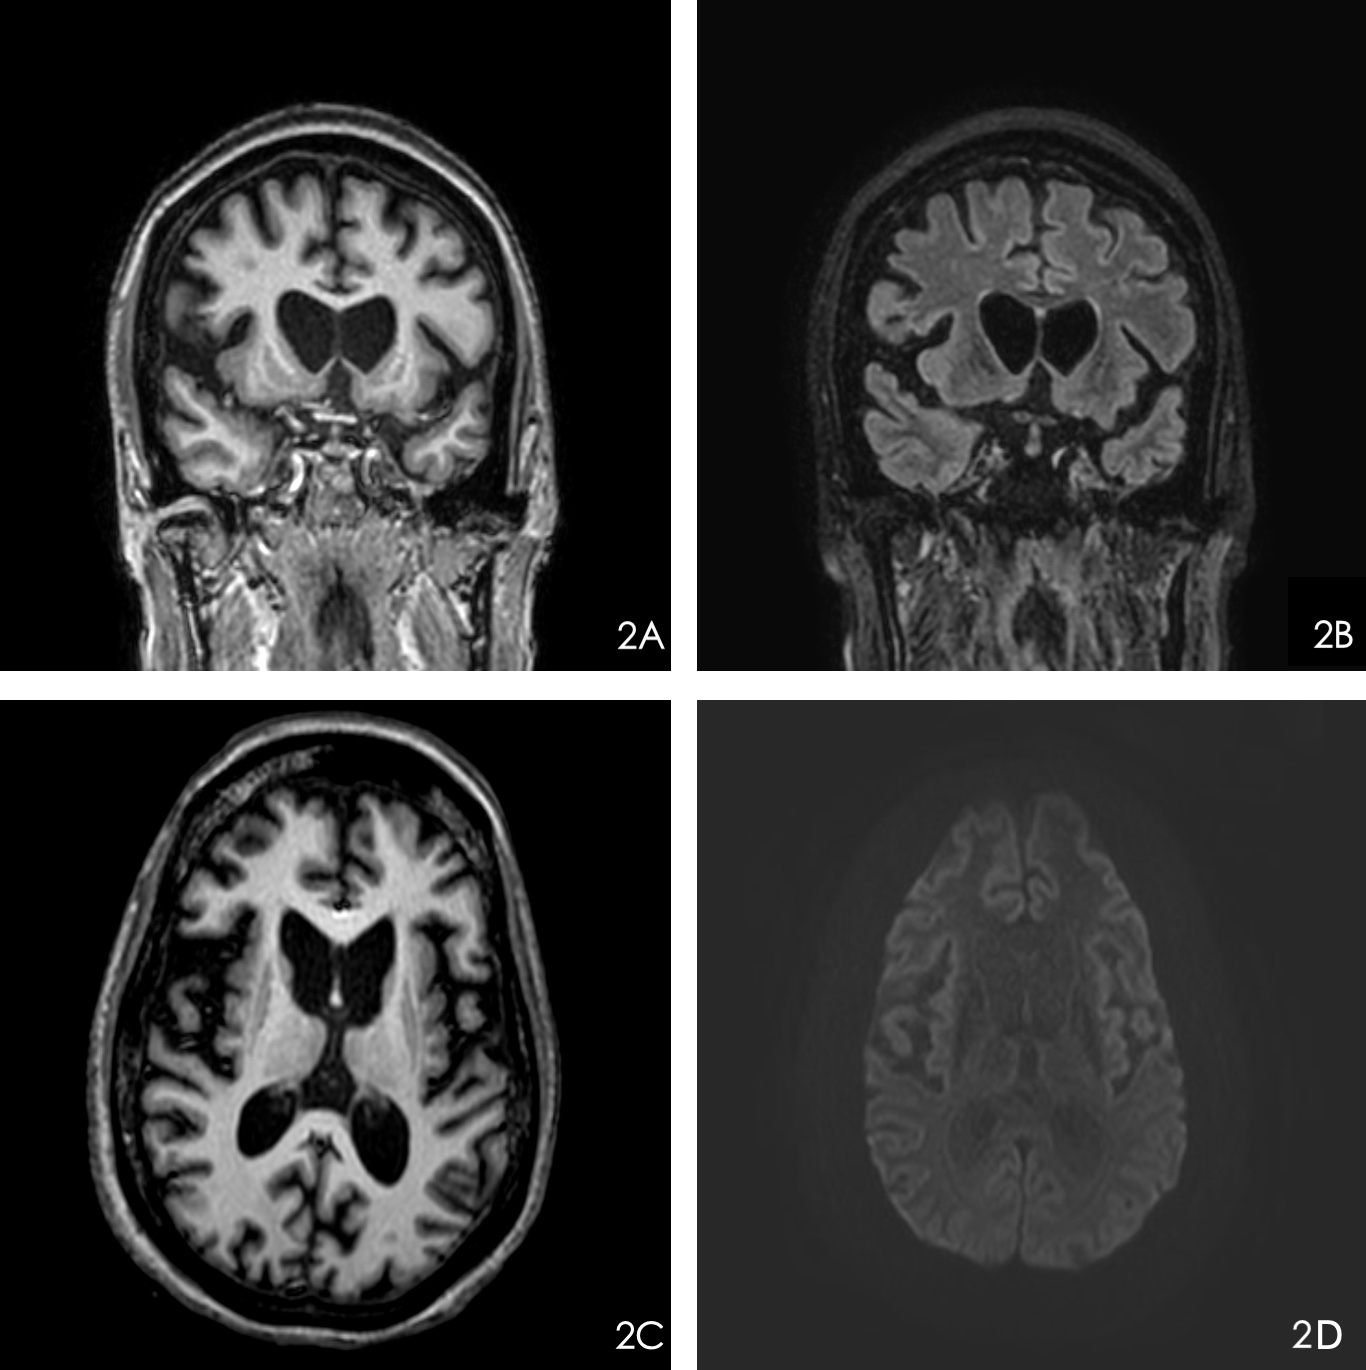

JE was a 30-year-old female with a paternal history of Huntington’s disease and was diagnosed with JHD at 19 years old, which was later confirmed by genetic testing. At her initial diagnosis, she had upper extremity chorea impairing her fine motor skills. The disease progressed to cause frequent falls, cognitive dysfunction, hypophonia, and orofacial dystonia. Epilepsy started at 20 years old, and she developed multiple seizure types, including: tonic-clonic seizures, seizure with impaired consciousness, and myoclonic seizures. She was longitudinally monitored with EEG and was found to have electrographic abnormalities, including: generalized spike and polyspike and slow wave discharges; myoclonic seizures; PR (Figure 1a); and EDB (Figure 1b). Her MRI brain without contrast showed severe bilateral caudate atrophy, diffuse cortical atrophy, and frontally predominant cortical diffusion restriction in the context of a recent seizure (Figure 2).  Despite treatment with multiple anti-seizure medications, her seizures remained medically refractory. Due to her progressive neurological deterioration, she was ultimately transitioned to hospice.